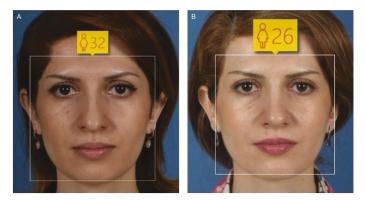

Actualité publiée le 25/02/2020RHINOPLASTIE : Pour « faire » 3 ans de moins ?

Actualité publiée le 08/02/2020